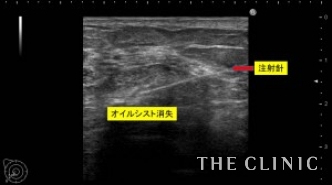

オイルシストは、壊死した脂肪がオイル状になったものですので、注射針で吸引可能です。

充実性のしこりは、壊死した脂肪が固まった状態ですので、ベイザーリポの特殊な超音波で崩して吸引しました。